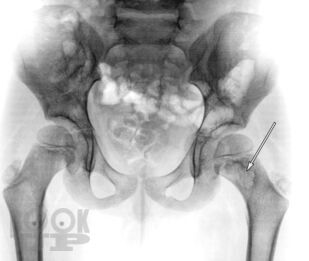

В пособии приводится общее описание одного из патологических состояний костно-суставной системы у детей — небактериального остеомиелита. В общем виде описаны современная теория развития данного заболевания, принципы диагностики и лечения, а также принципиальный тактический алгоритм при небактериальном остеомиелите.